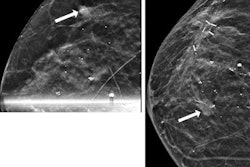

Ultrafast MRI images have potential to predict upstaging of DCIS lesions by measuring time to enhancement (TTE), according to research presented at the RSNA annual meeting. Image courtesy of Dr. Rachel Miceli.The researchers found that out of the total, seven DCIS lesions (11%) were upgraded to higher-grade DCIS. Another 26 lesions (38%) were upgraded to invasive cancer.

Also, upgrade to invasive cancer was significantly tied to shorter TTE on preoperative ultrafast MRI (p = 0.031). This includes an optimal threshold of 11 seconds, with 50% specificity and 76% sensitivity for upgrade. This is consistent with previous studies on TTE time. The team also found that needle gauge size (p = 0.049) and larger lesion size (p = 0.001) were linked to upgrade from DCIS to invasive cancer, with an optimal threshold of 4.35 cm.